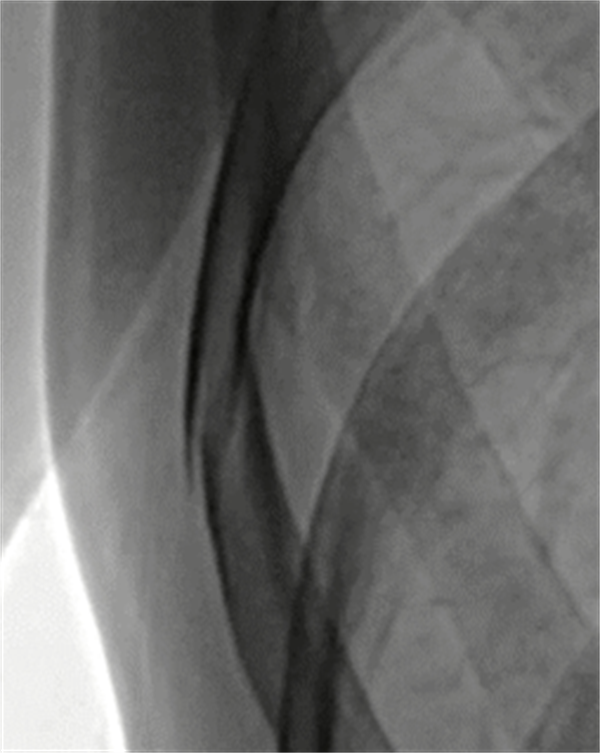

显然,静态DR并不能满足临床需求。以胃肠患者为例,这类患者常需要造影检查,但静态DR更多显示的是器官投影。单一角度及时间,较难发现细微病灶。随着DR技术的发展,更高效、更精准、更便捷的动态DR应运而生。

2013年,安健科技自主研发了中国首台动态DR,开启了国产设备动态DR时代。从功能方面上,动态DR是一款多功能DR,可以进行数字化x线摄影、数字化x线造影、数字化x线透视等,相较于静态DR,动态DR具备更多的临床应用场景。这种动态DR在业内又被称为“数字胃肠机”,主要用于消化道、泌尿及呼吸系统的造影检查。

(左为动态DR临床图像,右为上消化道造影图像)